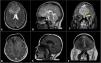

Central nervous system involvement by multiple myeloma is extremely rare and is diagnosed in less than 1% of cases. Differential diagnosis includes lymphomas, metastases, sarcomas, osteochondromas, hemangiopericytomas or meningiomas. We report a 46-year-old female with a history of multiple myeloma in apparent remission after autologous bone marrow transplantation, who consulted for a palpable mass in the frontal region associated with holocranial headache and decreased visual acuity of two months of evolution with imaging studies compatible with olfactory sulcus meningioma. A craniotomy and total resection of the lesion by bicoronal approach was performed and histological sections showed a neoplastic proliferation consisting of cells with a spherical nucleus and lateralized eosinophilic cytoplasm. Lesion compatible with involvement of the central nervous system by multiple myeloma. This case highlights the diagnostic challenge due to radiologic similarity with other tumours, especially meningiomas, and emphasizes including myeloma in differential diagnoses.